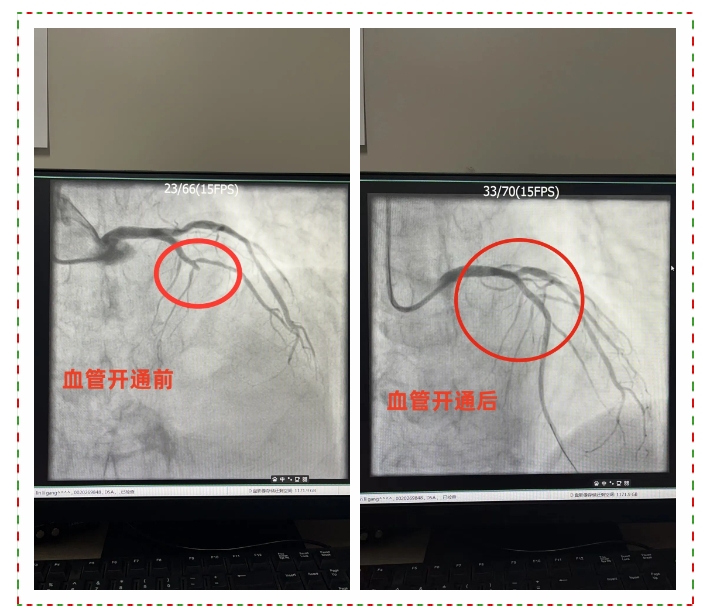

我院立即启动胸痛绿色通道,心内科王瑞利主任带领胸痛团队迅速为患者实施急诊冠脉造影检查,凭借丰富的经验和精湛的技术,快速开通闭塞的冠状动脉血管,完成支架植入。患者病情得到有效控制,转入CCU继续监护治疗。